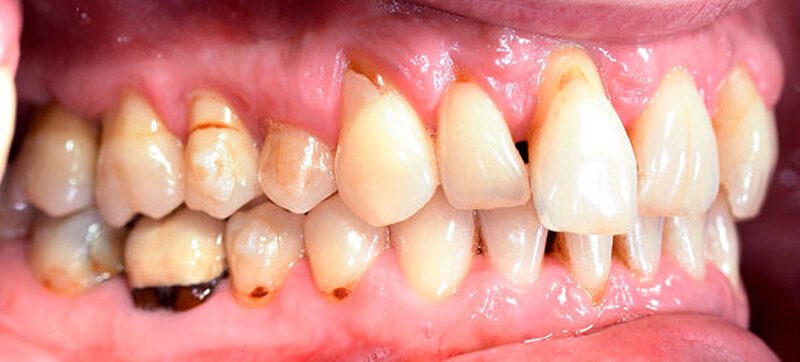

Anamnestisch lagen keine Besonderheiten vor. Es ist jedoch zu vermerken, dass ein regelmäßiger Alkohol-, Koffein- und Nikotinkonsum zugrunde lag. Intraoral zeigte sich ein bereits konservierend versorgtes permanentes Gebiss mit aktivem und inaktivem kariösen Geschehen. Große Anteile der Zahnhälse lagen nach Zahnfleischrückgang in Kombination mit Knocheneinbrüchen frei. Zahn 27 wurde bereits extrahiert.

Eine Beurteilung der parodontalen Situation an Zahn 11 offenbarte mesial und distal Sondierungstiefen von jeweils 6 mm.

Kieferorthopädisch imponierte beidseits eine neutrale Verzahnung bei einem tiefen Biss von 5 mm – bedingt durch die Verlängerung beider Frontzahngruppen. Besonders Zahn 11 zeigte eine erhebliche Verlängerung und Protrusion mit einer sagittalen Frontzahnstufe von 5 mm. Sowohl die Frontzähne im Ober- als auch im Unterkiefer wiesen eine lückige Beziehung zueinander auf (Abbildung 1).

Röntgenologisch stellte sich im Orthopantomogramm der bereits intraoral ersichtliche horizontale und vertikale Knochenabbau mit Attachmentverlust an einzelnen Zähnen dar. Die Erhaltungswürdigkeit einzelner Zähne war aufgrund des starken Knochenverlustes beziehungsweise der Beeinträchtigung des Halteapparates als kritisch zu beurteilen.